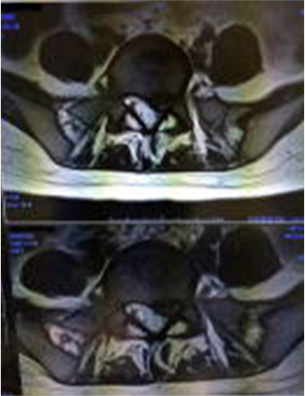

当院では、画像での診断も行っております

病院からレントゲン画像やMR画像を持参いただけるとより詳しい判断ができます。医師や医療関係者、他店の整体師や柔整師が自分の身体のメンテナンスのために来店する当院。宇都宮市の病院内で院長自ら施術をしていた経験もあり「安心」と「信頼の技術」が人気です。